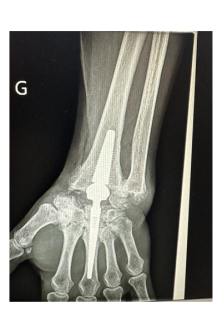

Pose de la 1ère prothèse de poignet de Roanne

Le Dr Ramy Belhaouane, chirurgien orthopédiste spécialiste du membre supérieur, pose la première prothèse de poignet de Roanne chez une patiente âgée de 63 ans.

L’intervention nécessite un geste chirurgical précis dont la durée varie entre 1h et 1h30 et peut se réaliser en ambulatoire. Le chirurgien vient remplacer les os du carpe par une prothèse afin de restaurer une certaine mobilité articulaire.